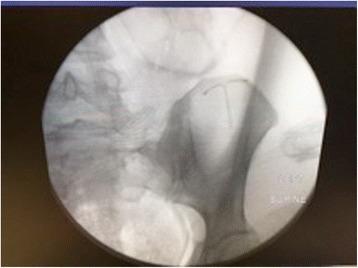

We present a case of an intrauterine device found in the omentum of a 30-year-old white postpartum woman with a significantly retroverted uterus after the intrauterine device threads were not visualized on speculum examination during a 6-week placement check. The intrauterine device was located and removed via laparoscopy without complication.